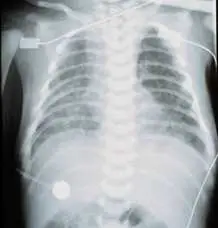

4天大男嬰,因呼吸急促及厲害發紺現象住院,胸部 X光檢查如圖所示。給予腎前列素( PGE 1 )後,其發紺及呼吸急促現象並未改善,下列何者為最可能的心臟問題? 圖片

胸部 X 光顯示:

• 心臟大小:心臟輪廓相對偏小(small heart),心胸比(cardiothoracic ratio)不大,無明顯心臟擴大

• 肺野:雙側肺野呈現瀰漫性霧狀(diffuse haziness),肺紋路增加,整體呈現典型的**肺靜脈鬱血及肺水腫(pulmonary venous congestion and edema)**表現,有「暴風雪(snowstorm)」樣外觀

• 縱隔:無明顯縱隔擴寬,無典型「雪人(snowman)」徵象(後者見於無阻塞型上腔型 TAPVR)

• 整體印象:「小心臟 + 嚴重肺水腫」的組合